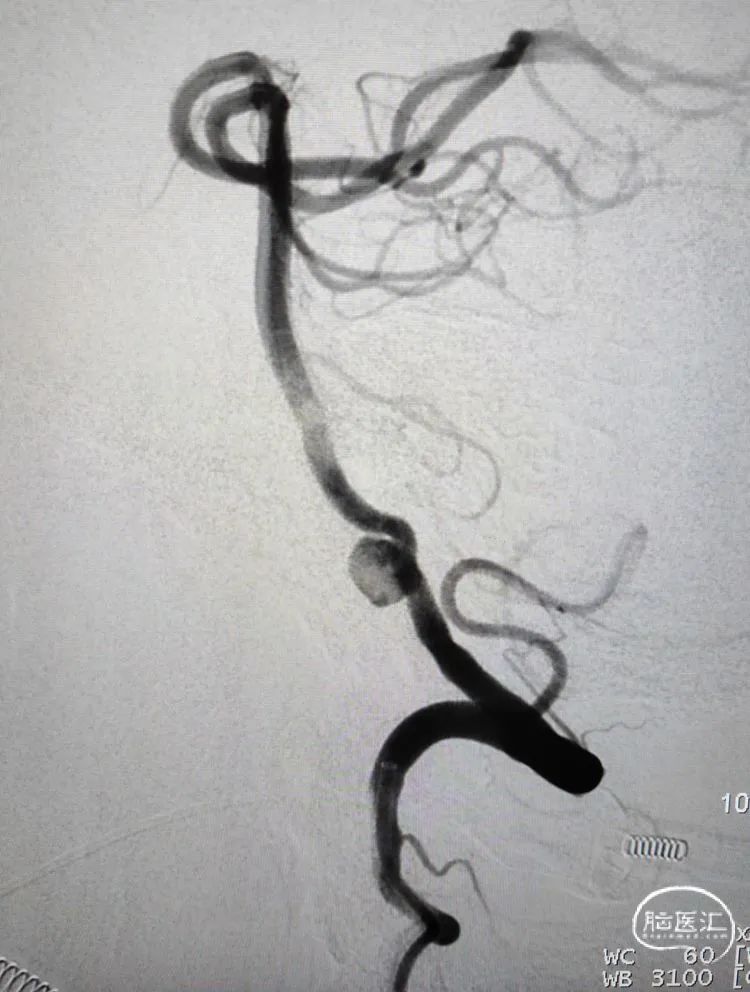

术前影像学检查:全脑血管造影检查提示右侧椎动脉V5段(颅内段)夹层动脉瘤。

动脉瘤大小约5.45mm×7.31mm,动脉瘤远端椎动脉汇合前管径约2.77mm,动脉瘤近端V4段管径约3.80mm,V5段全长约35mm,对侧椎动脉正常。

正位造影